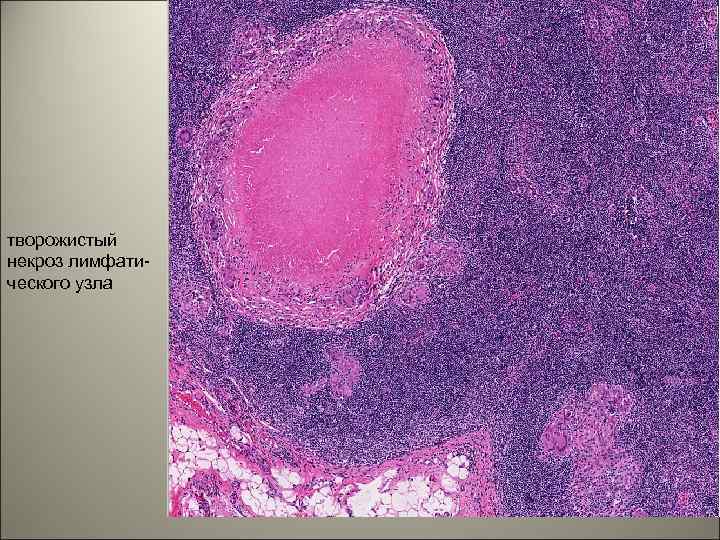

творожистый некроз лимфатического узла 33